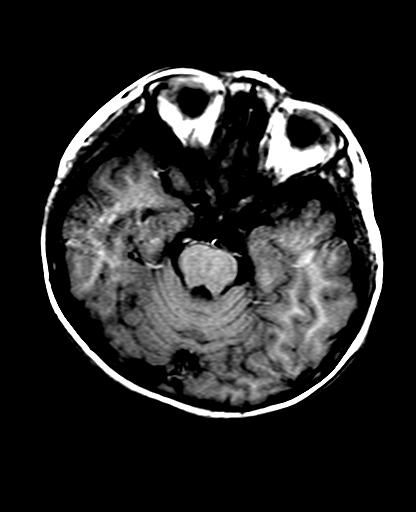

标题: PED2848:脑内病变2

头痛10天、间断呕吐2天。f 6岁

入科化验血清铜及铜兰蛋白均减低,脑脊液正常,血清神经原烯醇化酶明显增高。wbc:5.94x109/l、

临床表现及实验室检查符合肝豆状核变性

符合肝豆状核变性。

不排除肝豆状核变性可能。

mri未见明显异常。但临床支持考虑肝豆状核变性。